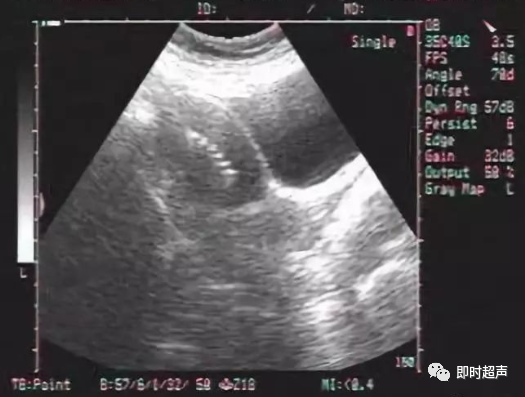

放置宫内节育器(IUD)后复查,B超是主要手段。

B超复查的内容主要包括两个方面,一是IUD位置是否下移,IUD位置下移将影响避孕效果;二是IUD是否嵌入子宫肌层,嵌顿将会增加疼痛、出血等副反应,也增加了IUD异位的风险。

支架与无支架IUD都存在着穿透子宫肌壁、浆膜层,造成子宫穿孔,IUD外移的风险。若超声扫查子宫内无IUD的强回声,而在宫旁、子宫直肠凹陷或腹腔内见强回声的IUD声像,提示IUD异位。

值得注意的是,有放置IUD,而无取出史的妇女,若超声提示宫腔内未见IUD,不要轻易认为IUD脱落,需做盆腔超声检查或X线检查,排除IUD异位。

发现IUD异位,应及时取出。腹腔镜或开腹取出前,IUD定位很重要。